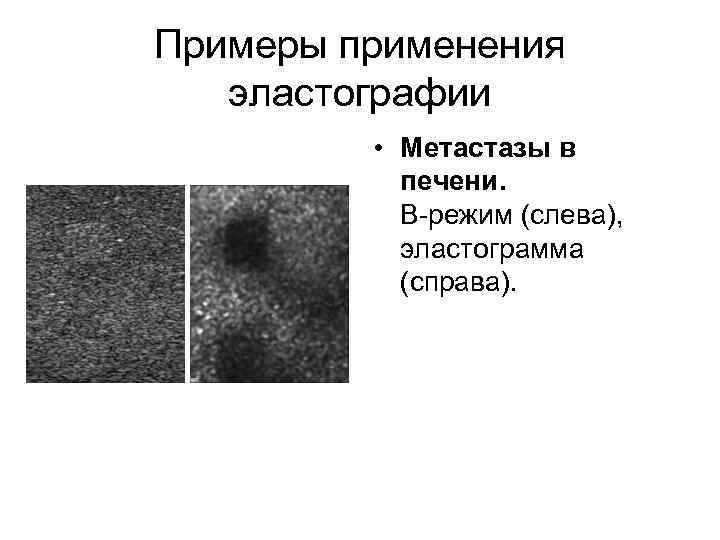

Примеры применения эластографии • Метастазы в печени. B-режим (слева), эластограмма (справа).

Примеры применения эластографии • Метастазы в печени. B-режим (слева), эластограмма (справа).